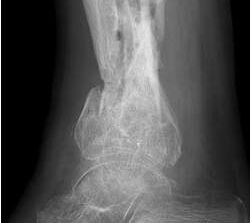

• Primäre oder posttraumatische Arthrose des OSG und USG (Abbildung 1, Abbildung 2).